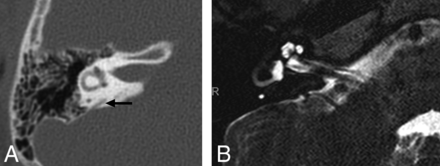

The third group had a diagnosis of EVA on HRCT with a diagnostic MR imaging available for review. This group included 24 patients and 48 ears, with an age range from 0.5 to 15 years (mean, 6.6 years; M/F ratio = 1:1.4). Three patients had a diagnosis of Coloboma of the eye, Heart defects, Atresia of the choanae, Retardation of growth and/or development, Genital and/or urinary abnormalities, and Ear abnormalities and deafness (CHARGE) syndrome. Bilateral EVA was present in 14 patients, and unilateral, in 10, with 38 ears having an EVA on CT (Fig 5). The mean VA size was 1.7 mm, and the median VA size was 1.6, with a range of 0–4 mm. By means of a cutoff of 1-mm midaperture width, only 1 ear was misdiagnosed as normal on MR imaging, with the ELD measuring 0.9 mm on MR imaging compared with the VA measuring 1.6 mm on HRCT (Fig 6). All normal VAs on CT were measured as normal ELDs on MR imaging. With HRCT as the standard, sensitivity for demonstrating an enlarged ELD using MR imaging was 97% (95% CI, 86%–100%) with a specificity of 100% (95% CI, 69%–100%) for the first reader. For the second reader, sensitivity was 89% (95% CI, 75%–97%) and specificity was 90% (95% CI, 56%–100%). Intraclass correlation coefficients calculated for interrater agreement were 0.89 (95% CI, 0.81–0.93) on MR imaging and 0.91 (95% CI, 0.84–0.95) on CT.

Axial HRCT (A and B) shows the vestibular (V) and opercular (O) planes used to define the VA midpoint (M), and an EVA measuring 1.3 mm (arrow). MR imaging (C and D) in the same patient shows the corresponding vestibular (V), opercular (O), and midpoint (M) planes and an enlarged ELD measuring 1.2 mm (arrow).